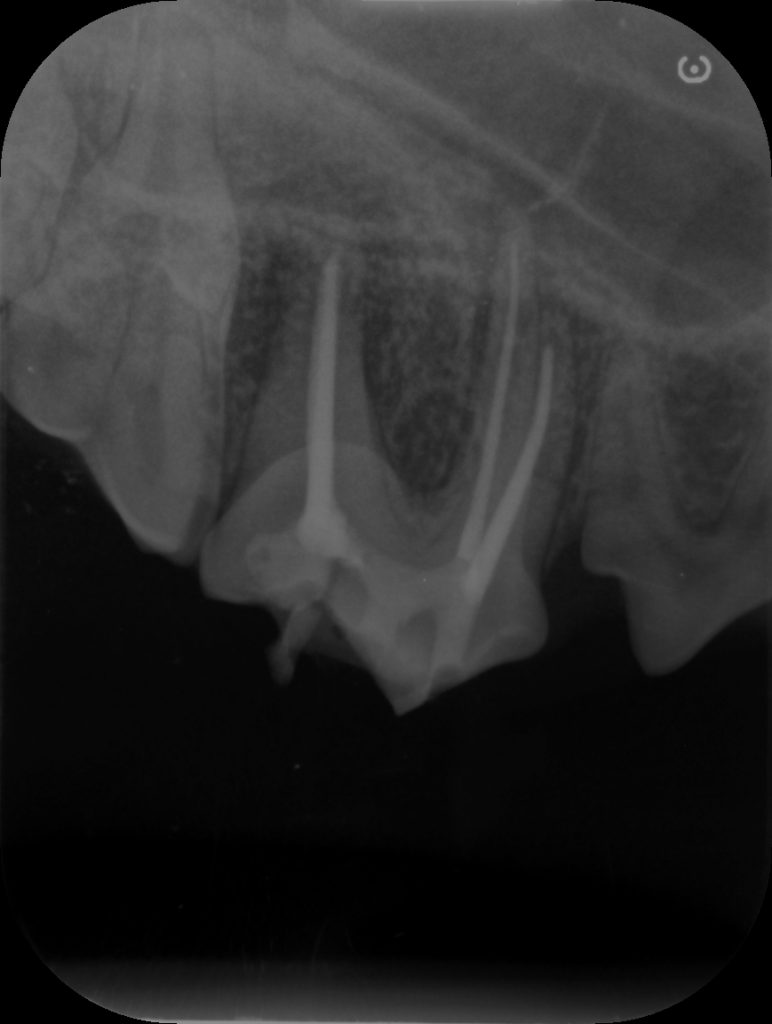

処置が終わるとこのように神経のあった管に白いものが詰まっている状態になっています。これにより汚いものが根っこの先から出ないようにできます。

この治療では、根っこの先の細かい管までは削れない事や根っこの先の周囲についた汚れまでは取れないため必ず治るとは限りません。状態によりますがおおよそ8~9割ぐらいの可能性で治ると思いますが、成功したかどうかは数年しないとわかりません。

処置直後の歯です。歯茎の裏まで割れていたため歯茎の裏まで処置をしています。

レントゲンではまだ以前の骨の変化は残っていましたが根尖周囲の骨が白さを増している状態でしたので今のところ悪化はないと判断できます。